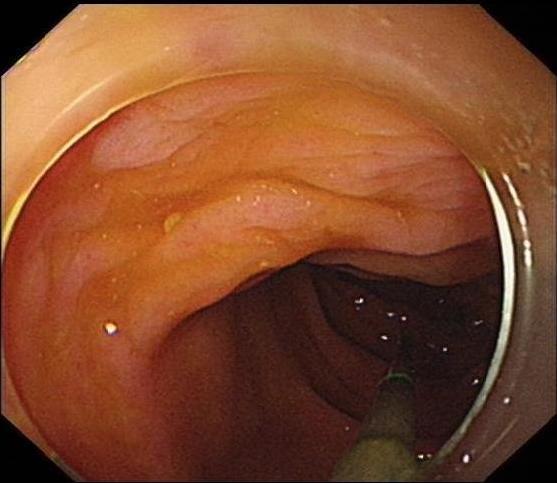

2.2 术前准备及术中配合根据无痛胃肠镜要求,对患者进行肠道准备及禁食禁饮宣教,护士加强患者心理支持,并做好仪器设备准备,如抢救车、除颤仪等。结肠镜前端置透明帽后循腔进镜,经直肠、乙状结肠、降结肠、横结肠时,见1个条形金属异物,长约3 cm(图 7),观察到一端已插入肠壁,首先选用异物钳将插入尖锐端金属轻轻拔出。为避免金属钻易脱落,强行取出异物容易造成肠道二次损伤,改用圈套器将尖锐端套住收紧后拉入透明帽内配合医生不断变换角度,调整方向,使异物方向和镜身尽量保持平行(图 8)缓慢通过各结肠弯曲部,顺利将异物取出(图 9)。整个内镜操作过程只用了15 min,无出血和穿孔等并发症发生。

| 图 7 通过横结肠,可见尖锐异物 |